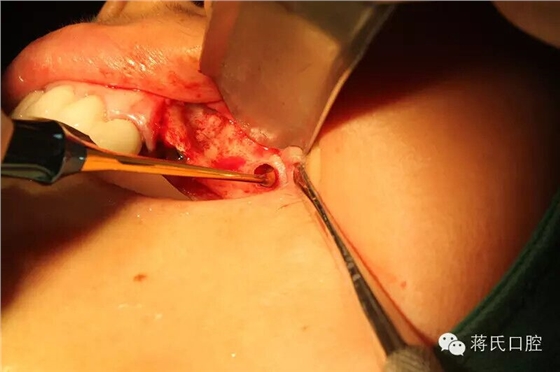

10.左側(cè)切開(kāi)后

11.第一洞制備完成

12.左側(cè)外提升過(guò)程